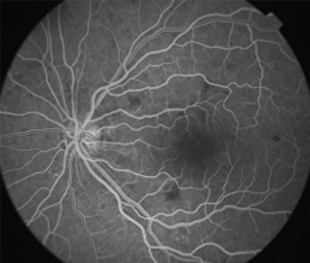

Angiografía OD

Angiografía OI

- Angiografía: teñido arterial, escape capilar, más tardíamente, no perfusion arteriolar y venular con teñido de las paredes vasculares y dilatación venosa.